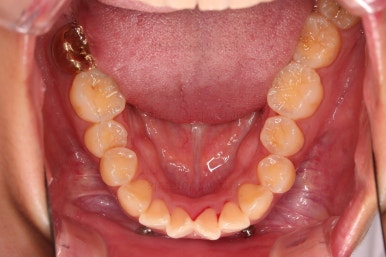

3. 치료경과

아래 앞니는 장치 부착 이전에 아래로 앞니를 내려줄 미니스크류를 식립했습니다.

미니스크류가 단단하게 붙었을 시점에 아래 앞니도 장치를 부착하고요.

과개교합 개선을 위해서 미니스크류까지 힘을 줘서 아래 앞니를 내려줍니다.

아래 앞니는 브라켓보다는 훨씬 작은 미니튜브 장치를 사용했습니다.

과개교합의 경우 브라켓을 부착하게 되면 씹히게 되어 치료과정이 수월하지 못하기 때문이죠.

디테일을 위해서 윗니는 어금니에도 하나씩 장치를 더 부착했고, 아랫니는 바로 뒷 치아에도 장치를 부착했습니다.

과개교합 개선에 미니스크류까지 사용되었던 터라 매우 난이도가 높은(전체교정보다 훨씬 난이도가 높습니다.) 부산앞니부분교정이어서 1년여의 기간이 걸렸는데요.

기왕(부분교정임을 감안했을 때) 오래 걸린거 좀 더 완성도를 높이고자 아래 앞니는 설측교정까지 부착했습니다.

역시 미니튜브 장치를 이용했고, 아래 앞니 안쪽에다가 장치를 부착해서 아주 미세한 배열을 맞춰드렸습니다.